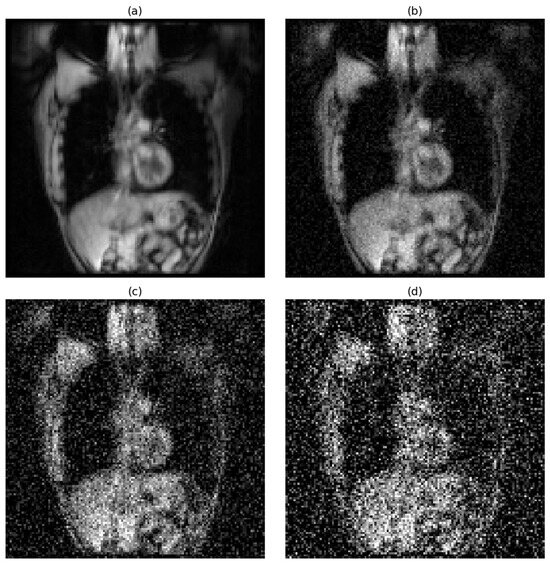

To quantify the level of image degradation introduced by noise, we calculated the average signal-to-noise ratio (SNR) for the central slice across all participants, assuming that the SNR patterns observed in central slices are representative of the entire slice stack. For hyperpolarized gas MRI, under noise-free conditions, the average SNR was 74, indicating excellent image quality. When Gaussian noise with a standard deviation of 0.05 was applied, the SNR dropped to approximately 19. Medium noise (std = 0.15) further reduced the SNR to 9.6, while high noise (std = 0.25) lowered it to 4.5. According to the Rose criterion, an SNR of 5 or greater is generally required for reliable object detectability in noisy images. Notably, the high noise level in our experiments fell below this threshold, providing a meaningful scenario to test the robustness of segmentation models under clinically challenging conditions.

The effects of progressive noise addition on image quality are visually demonstrated in Figure 1 for hyperpolarized gas MRI and Figure 2 for proton MRI.

Figure 1. Effect of Gaussian noise on hyperpolarized gas MRI image quality. Representative coronal slice showing progressive image degradation with increasing noise levels: (a) noise-free conditions (SNR = 74), (b) low noise with a standard deviation of 0.05 (SNR ≈ 19), (c) medium noise with a standard deviation of 0.15 (SNR = 9.6), and (d) high noise with a standard deviation of 0.25 (SNR = 4.5).